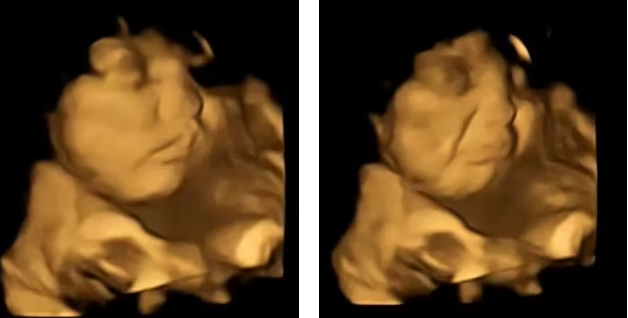

وأظهرت النتائج كيف ابتسم الجنين بعد فترة وجيزة من أكل الأم للجزر، على العكس مما فعل عند تناول الكرنب.

وأظهرت النتائج، أن كمية صغيرة فقط من نكهة الجزر أو الكرنب كانت كافية لتحفيز تفاعل الأجنة. وعندما تناولت النساء الجزر، كانت الأجنة تميل إلى الابتسام عند الفحص، بخلاف رد فعلهم عند تناول كبسولة الكرنب، حيث كانت تميل إلى التجهم.

قالت المؤلفة الرئيسية بيزا أوستون: "كان من المدهش حقًا رؤية تفاعل الأطفال الذين لم يولدوا بعد مع نكهات اللفت أو الجزر أثناء الفحص ومشاركة تلك اللحظات مع والديهم".